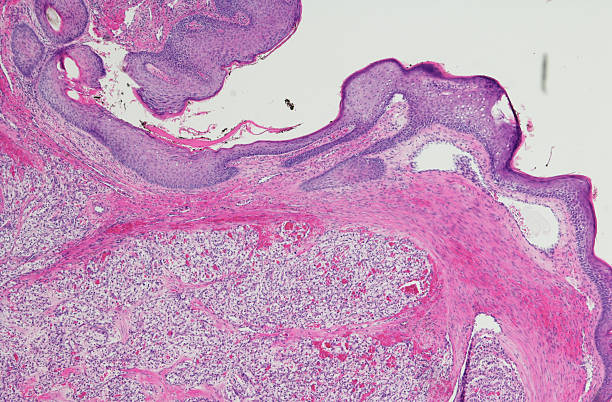

3. 물혹

물혹은 신장에서 발생하는 낭종으로, 별다른 증상이 없을 수 있습니다. 하지만 이러한 낭종이 발견될 경우, 신장암으로 진행할 가능성이 있는 경우도 있습니다. 따라서 물혹이 있는 경우에도 정기적인 검사를 통해 신장의 건강 상태를 모니터링하고, 필요한 경우 추가 검사를 받는 것이 중요합니다.